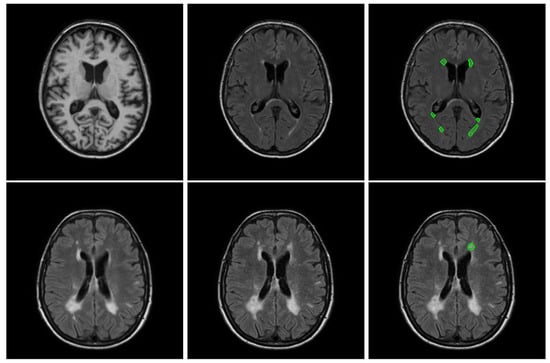

2.1.1. White Matter Hyperintensities (WMH) Challenge 2017 [4]

2.1.2. Ljubljana Longitudinal Multiple Sclerosis Lesion Dataset [1]

2.1.3. Data Preparation